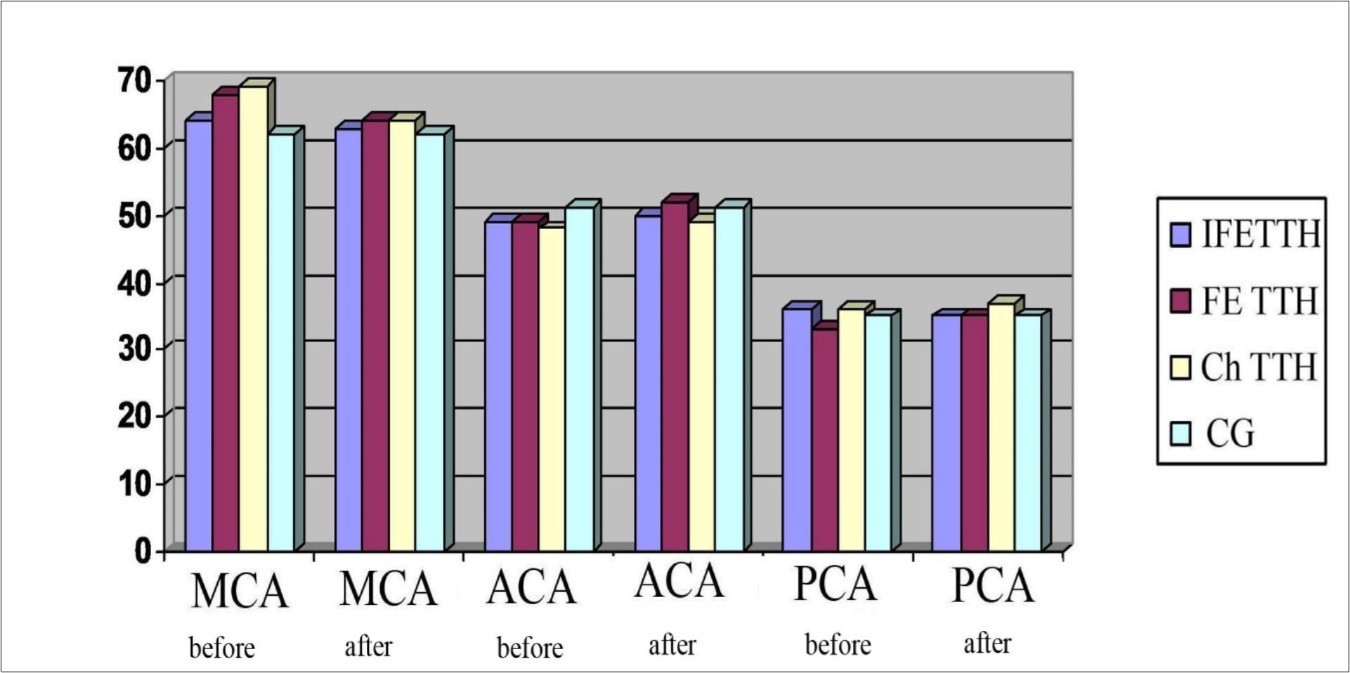

The asymmetry of the maximum systolic blood flow velocity (Vs) in the paired arteries within 20-30% was considered a violation of cerebral hemodynamics, which was detected in 38.7% of patients. An increase in Vs was noted in MCA in patients with Ch TTH and FE TTH compared with the control group (Figure 1, Figure 2A and B).

The pharmacotherapeutic effect of Noofen on the dynamics of blood flow indices in the main cerebral arteries is shown in Figure 8. The average value of the Vs in all groups before and after treatment was differented not significantly.

Figure 8.Dynamics of Vs in MCA, ACA, PCA in a patients with TTH during treatment with Noofen

The pharmacotherapeutic effect of drug on the dynamics of blood flow indices in the vertebral and basal arteries before and after treatment is shown in Figure 9. The minimal statistical significance (P<0,05) was observed only in the VA (from 41.4±1.3 cm/s to 37.2±1.4 cm/s).

Figure 9.Dynamics of Vs in VA and BA in a patients with TTH during treatment with Noofen